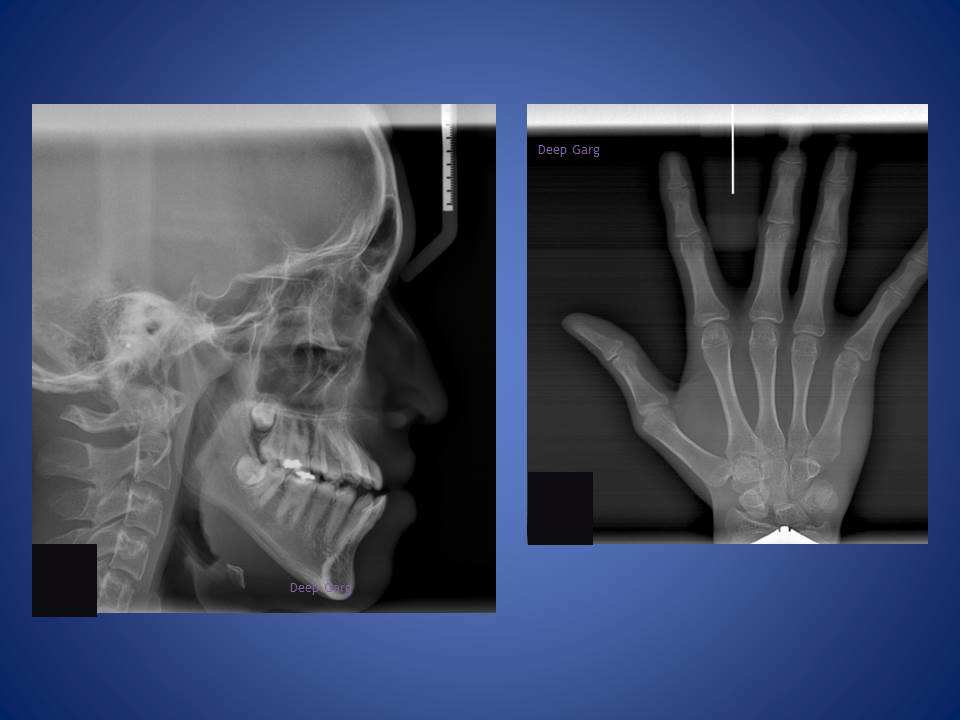

6.Lower jaw when forward can be corrected with the help of reverse pull head gear when treated at young age of 12-14 in boys and 10-12 yrs in girls. excellent result achieved here!!!